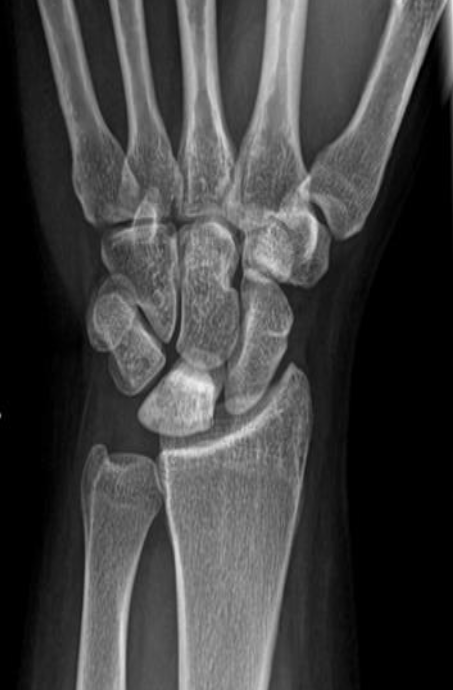

Polycystic kidneys disease

CT abdomen (with contrast; coronal plane) Both kidneys are markedly enlarged and feature multiple round-to-ovoid, hypodense lesions of various sizes compatible with cysts. Some smaller cysts are present in the liver.

The CT features are consistent with autosomal dominant polycystic kidney disease (ADPKD).

2nd img Polycystic kidneys disease CT scan, taken after intravenous contrast enhancement, showing that both kidneys are greatly enlarged and almost entirely replaced by cysts of variable size.